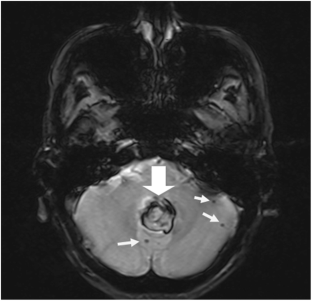

Maia LF, Magalhaes R, Freitas J, Taipa R, Pires MM, Osorio H, Dias D, Pessegueiro H, Correia M, Coelho T (2015) CNS involvement in V30M transthyretin amyloidosis: clinical, neuropathological and biochemical findings. J Neurol Neurosurg Psychiatry 86(2):159–167. https://doi.org/10.1136/jnnp-2014-308107

Sekijima Y, Yazaki M, Oguchi K, Ezawa N, Yoshinaga T, Yamada M, Yahikozawa H, Watanabe M, Kametani F, Ikeda S (2016) Cerebral amyloid angiopathy in posttransplant patients with hereditary ATTR amyloidosis. Neurology 87(8):773–781. https://doi.org/10.1212/WNL.0000000000003001

Sakashita N, Ando Y, Jinnouchi K, Yoshimatsu M, Terazaki H, Obayashi K, Takeya M (2001) Familial amyloidotic polyneuropathy (ATTR Val30Met) with widespread cerebral amyloid angiopathy and lethal cerebral hemorrhage. Pathol Int 51(6):476–480

Ushiyama M, Ikeda S, Yanagisawa N (1991) Transthyretin-type cerebral amyloid angiopathy in type I familial amyloid polyneuropathy. Acta Neuropathol 81(5):524–528